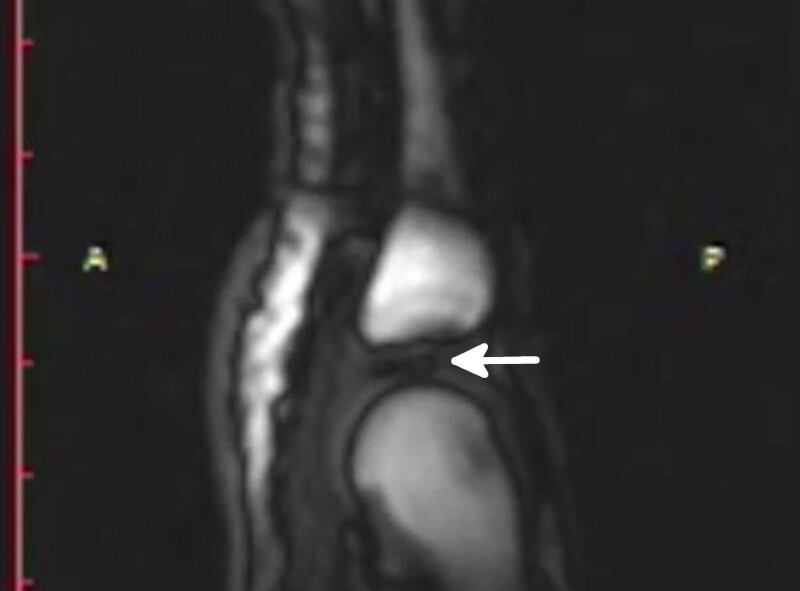

Los científicos pusieron los dedos de voluntarios en un dispositivo que tiraría con un cable de su extremo, con el objetivo de provocar el crujido, y los metieron dentro de una máquina de imagen por resonancia magnética. Los resultados se grabaron en vídeo.

Como vemos, el tirón del dispositivo provoca que los dos huesos del dedo se separen, hasta que “crujen” y vuelven a chocar entre sí. Lo interesante llega cuando vemos que ambos huesos acaban más distantes el uno del otro que antes de crujir, y que al instante se forma una zona oscura en la imagen.

La nueva hipótesis es que esa zona oscura entre los huesos son gases que se forman cuando los huesos chocan entre sí después de ser separados, y también que es esta formación repentina de gases lo que provoca el reconocible sonido. Por lo tanto, no es que se creen burbujas por si solas y las estallemos, es que las creamos cuando nos crujimos los dedos.